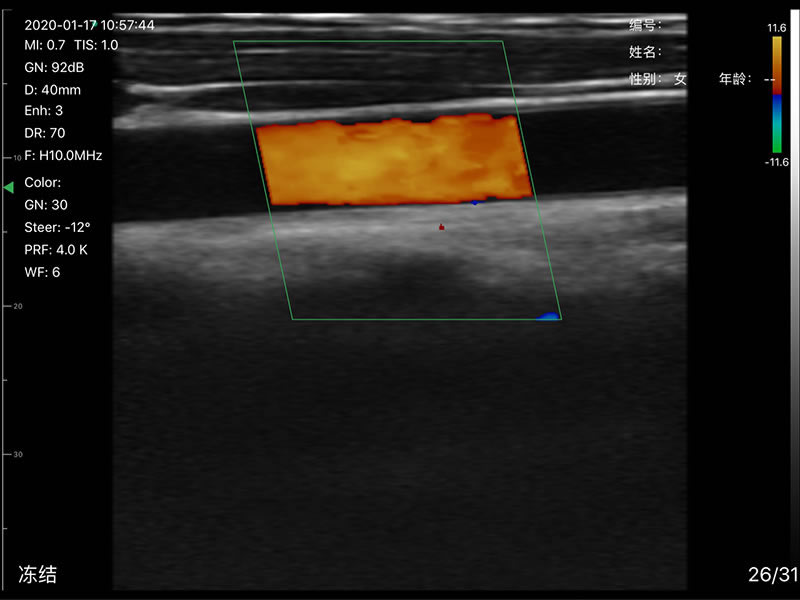

• 显示模式:B、B/M、Color、PW、PDI

• 探头频率:相控阵2.2/3.6MHz,线阵7.5/10 MHz

• 扫描深度:相控阵20-240mm,线阵 20-100mm,可调